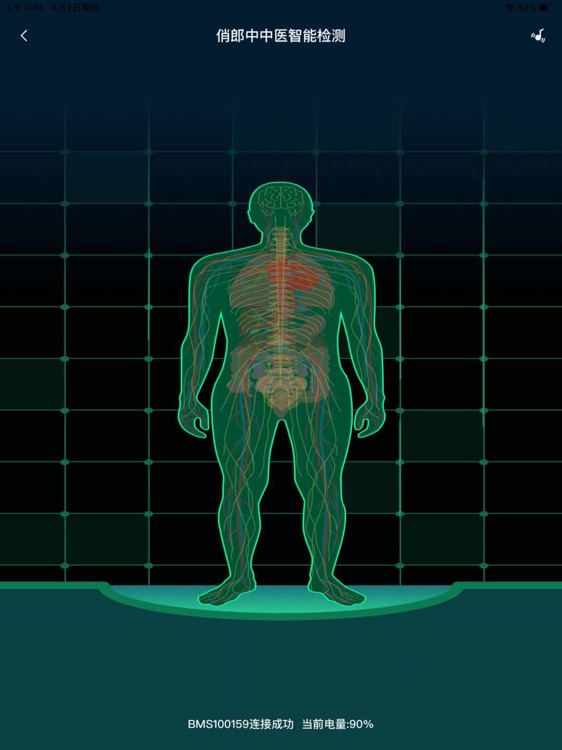

俏郎中专注于为大众提供优质中医服务。“俏郎中中医人工智能脉诊仪"可有效模拟知名中医、教授把脉结果,对个人健康状况进行全方位的评估及预警,做到“早评估、早发现、早干预、早治疗”。“一站式中医药在线健康服务平台”app为用户提供在线咨询、问诊服务,由公立医院中医师解答用户健康问题,分享保健气功、食疗药膳、治病偏方等各类养生内容,帮助大家改善体质、提高免疫力。

俏郎中专注于为大众提供优质中医服务。“俏郎中中医人工智能脉诊仪"可有效模拟知名中医、教授把脉结果,对个人健康状况进行全方位的评估及预警,做到“早评估、早发现、早干预、早治疗”。“一站式中医药在线健康服务平台”app为用户提供在线咨询、问诊服务,由公立医院中医师解答用户健康问题,分享保健气功、食疗药膳、治病偏方等各类养生内容,帮助大家改善体质、提高免疫力。

俏郎中专注于为大众提供优质中医服务。“俏郎中中医人工智能脉诊仪"可有效模拟知名中医、教授把脉结果,对个人健康状况进行全方位的评估及预警,做到“早评估、早发现、早干预、早治疗”。“一站式中医药在线健康服务平台”app为用户提供在线咨询、问诊服务,由公立医院中医师解答用户健康问题,分享保健气功、食疗药膳、治病偏方等各类养生内容,帮助大家改善体质、提高免疫力。